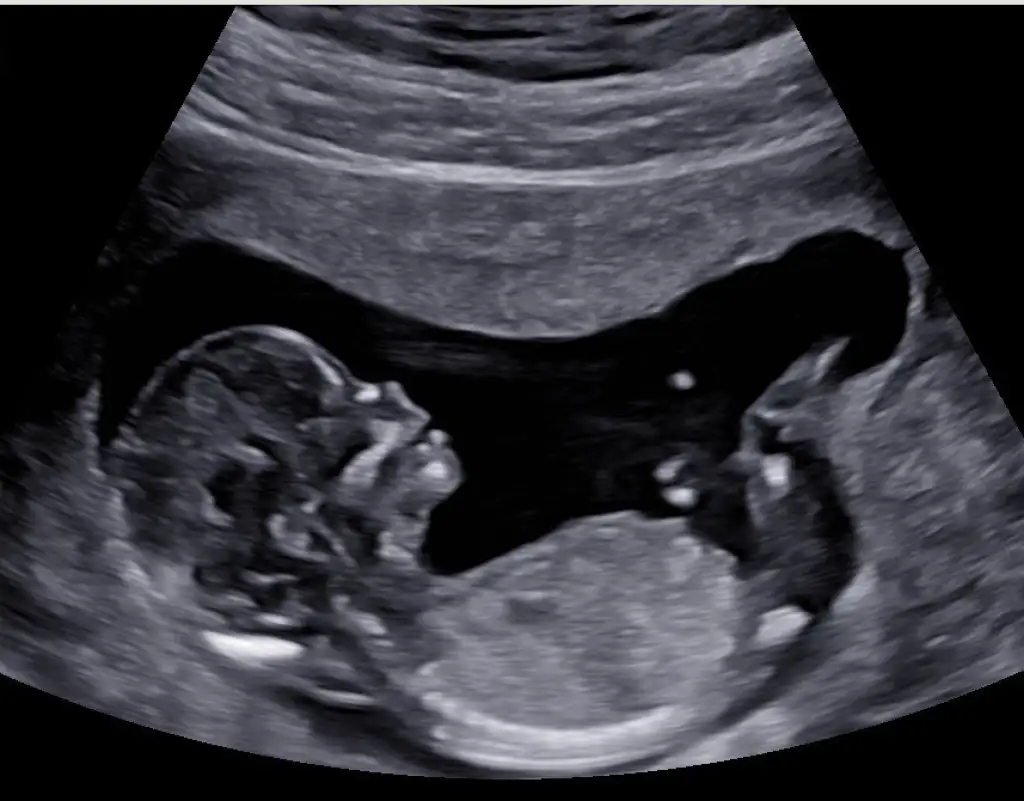

11+3’ten selamlar bugün kontrolümüz vardı, geriye yolunda dedi doktor, ikiz olduğu için de tarama testlerinin geçerli olmayacağını söyledi. Fetal DNA yaptırmamı önerdi. 12. Haftayı tamamlayıp öyle kan vereceğim, ikiz olduğu için her yer çalışmıyormuş, hem de miniklerin DNA sı biraz daha çoğalsın dedi. Ultrason görüntülerimizi de paylaşıyorum. Miniklerin cinsiyetleri ile ilgili tahmininiz var mı

Benim tek bebek olmasına rağmen fetal dna yaptırdım, iyi ki de yaptırmışım. bebeklerin biri kız biri erkek bence ama daha küçükler tam belli değil